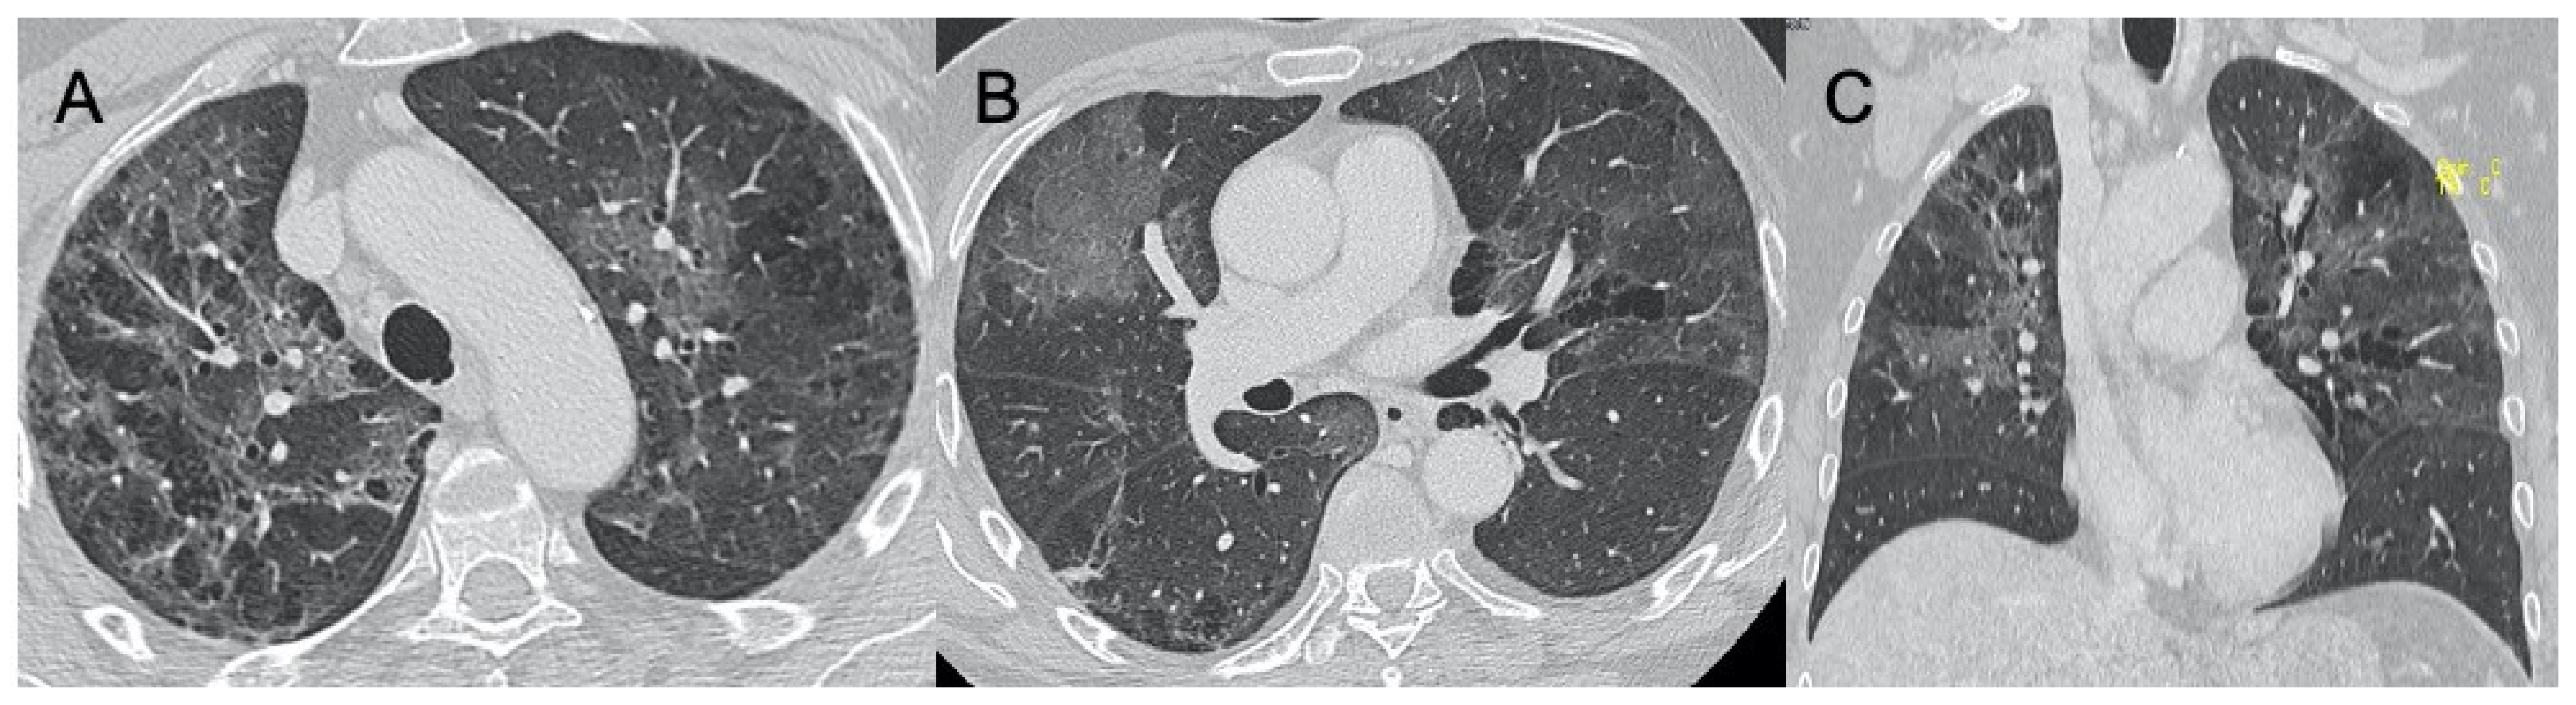

| Cytomegalovirus | Diffuse and bilateral consolidations with interstitial involvement. | Interstitial and alveolar infiltrates, bilateral and asymmetric GGO areas in association with areas of parenchymal consolidation | Figure 8 |

| Epstein-Barr virus | Lymphadenopathies with smooth interstitial parenchymal involvement in both lungs | Lymphadenopathies and less frequently interstitial infiltrates with diffuse GGOs and consolidations | Figure 9 |